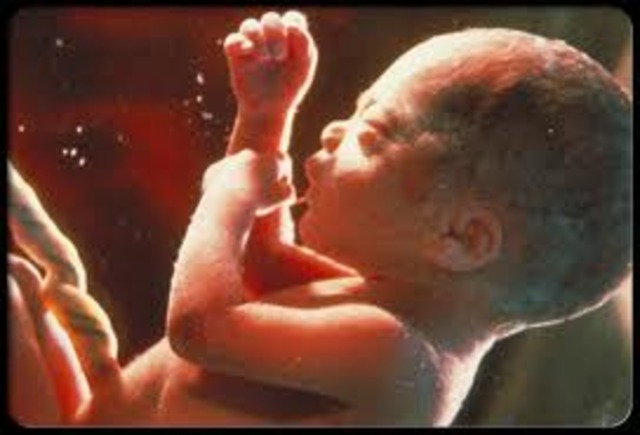

• Month 9

Month 9

• The baby is 17 to 18 inches long and weighs 5 to 6 pounds.

• The weight gain continues until the week before birth.

• The skin becomes smooth as fat deposits continue.

• The movements decrease as the fetus has less room to move around.

• The baby aquires disease-fighting antibodies from the mother's blood.

• The baby will descend into pelvis, ready for birth.